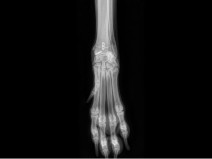

• 19ème Cours de Propédeutique, sémiologie et pathologie de l'appareil locomoteur - Carpe, tarse et au-delà : explorons les extrémités

Le thème de cette 19ᵉ édition du Cours de Propédeutique, Sémiologie et Pathologie de l’Appareil Locomoteur à Bédoin sera d’explorer les extrémités. Nous poursuivons l’objectif qui fait la force de ce rendez-vous depuis ses débuts : offrir une approche à la fois rigoureuse, pratique et actuelle des affections locomotrices. À travers un programme structuré mêlant rappels fondamentaux, analyse sém...